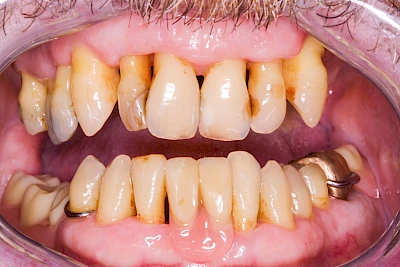

Ist zunächst nur das Zahnfleisch von der Entzündung betroffen, spricht man von Gingivitis. Später, wenn auch der Knochen um die Zähne herum entzündet ist, spricht man von einer Parodontitis. Bei der Parodontitis wird der Knochen nach und nach abgebaut und das Zahnfleisch zieht sich zurück. Die Zahnhälse und Zahnwurzeloberflächen liegen mehr und mehr frei. Die Zähne werden zunehmend lockerer und fallen schließlich aus.